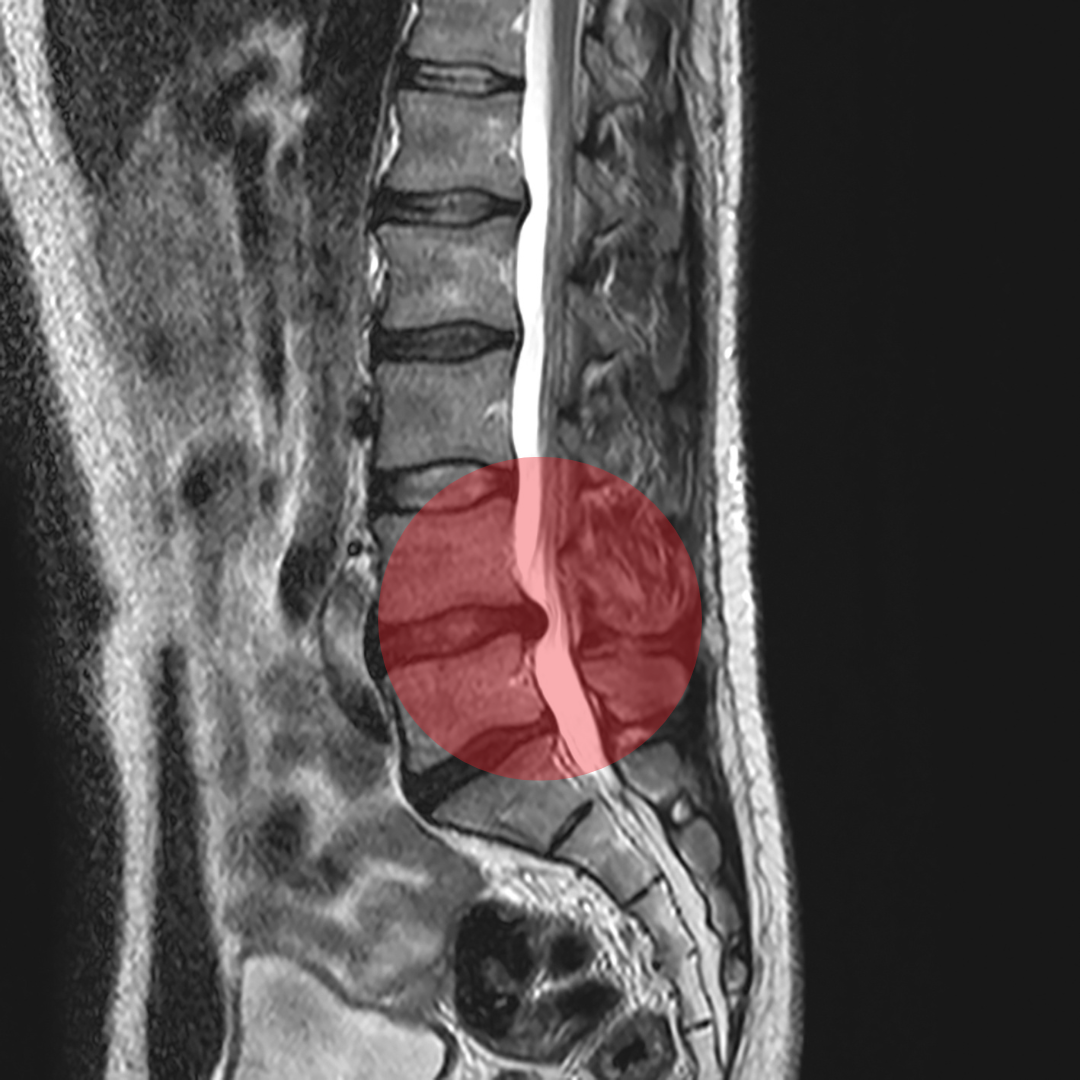

O Trata Coluna é um programa de tratamento altamente eficaz que utiliza técnicas baseadas em protocolos cientificamente comprovados, que possuem um alto índice de melhora. O objetivo principal é amenizar as dores, melhorar a mobilidade da coluna e restabelecer a estabilidade da mesma. Com profissionais qualificados e especializados, o Trata Coluna oferece um atendimento personalizado e individualizado, levando em consideração as necessidades específicas de cada paciente. Através de sessões regulares e acompanhamento constante, buscamos proporcionar resultados efetivos e duradouros, visando a qualidade de vida e o bem-estar dos nossos clientes. Com o Trata Coluna, você pode contar com um tratamento seguro, confiável e respaldado por pesquisas científicas, para cuidar da saúde da sua coluna de forma eficiente e profissional.